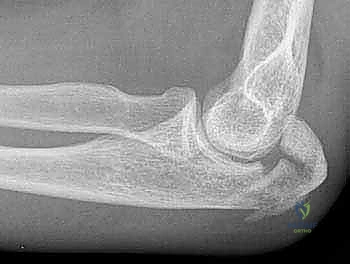

Image

TECH FIG 3 • A. A lateral radiograph illustrates a comminuted olecranon fracture with a small proximal olecranon fragment. B. An oblique view shows the fragmentation. C. A 3.5-mm limited-contact dynamic compression plate and screws contoured to wrap around the dorsal surface of the olecranon is used for fixation. (continued)